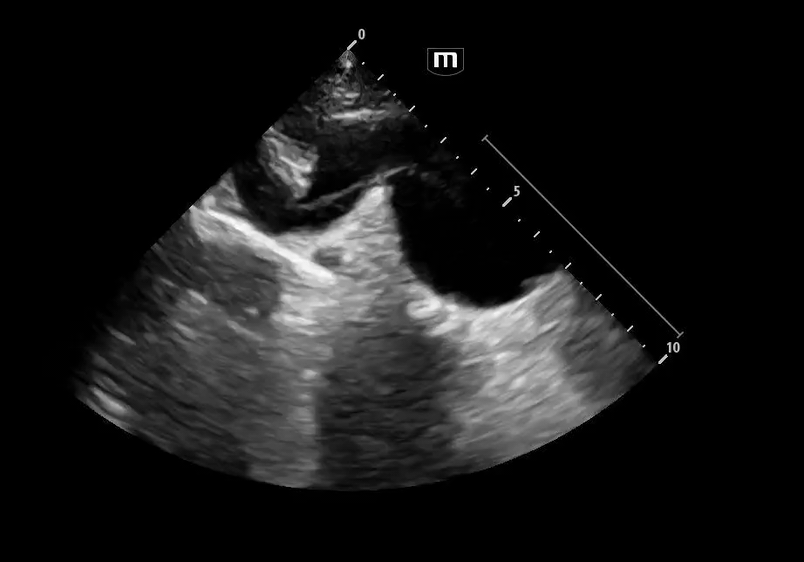

Image 3 - 5: Suprasternal notch

Interpretation: Dilated aortic arch including both ascending and descending aorta with linear echogenic structure within the lumen consistent with an intimal flap, as well as appearance of true and false lumens within the arch.

Ultrasound Findings in Aortic Dissection

• Intimal flap within the lumen

• Double lumen appearance

• Ascending aortic dilation

• Aortic arch involvement on suprasternal view